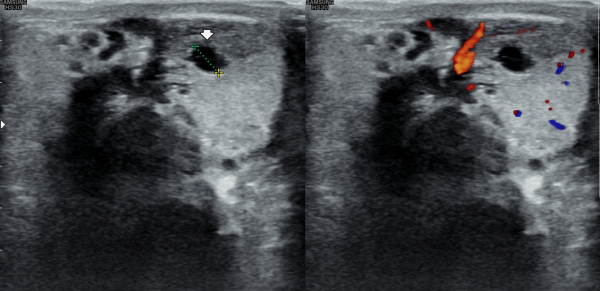

5년전부터 폐암으로 투병중 전립선 치료를 받지 못하던중 최근 하복부 통증이 심해져 내원 당일 추적 경직장 전립선 초음파 추적 검사상

전립선 낭종들이 커지고 사정관 입구의 미세 결석이 관찰되는 사진입니다.

A follow-up transrectal prostate ultrasound image taken on the day of the visit shows enlargement of prostatic cysts and microcalcifications at the opening of the ejaculatory duct in a patient who had been unable to receive prostate treatment due to lung cancer for the past five years and recently developed worsening lower abdominal pain.